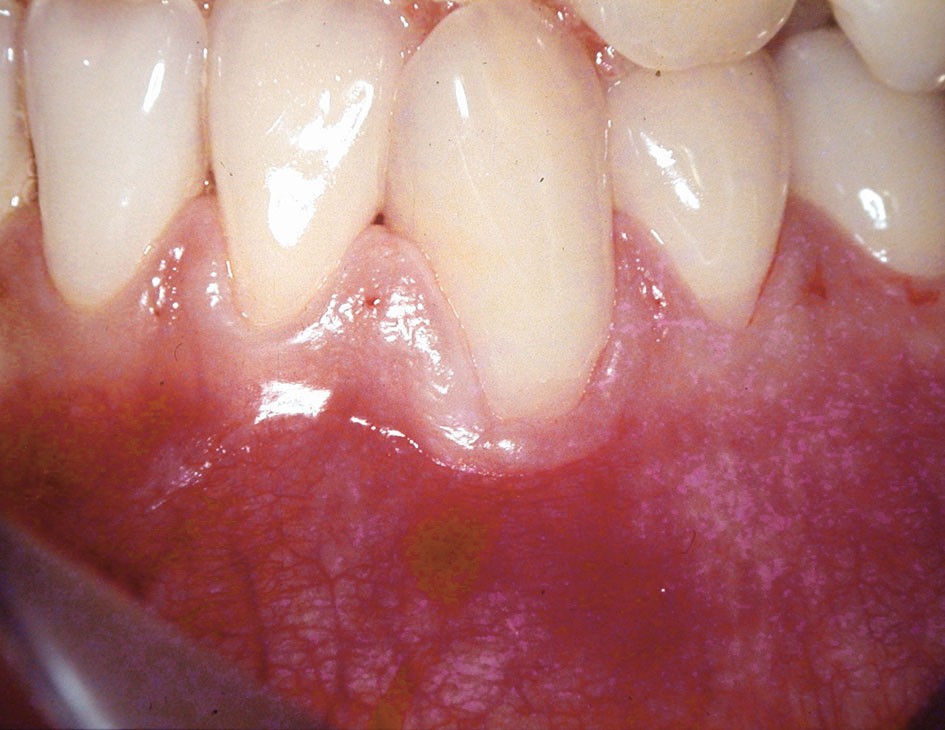

Dans ce premier cas, la présence d’un complexe muco-gingival inadéquat (fig. 1) est observée sur une canine et une prémolaire.

Cette absence de gencive attachée peut prédisposer à la formation d’une récession gingivale. Une greffe épithélio-conjonctive est réalisée. Elle permet d’obtenir un lambeau de gencive attachée kératinisée stable (fig. 2).